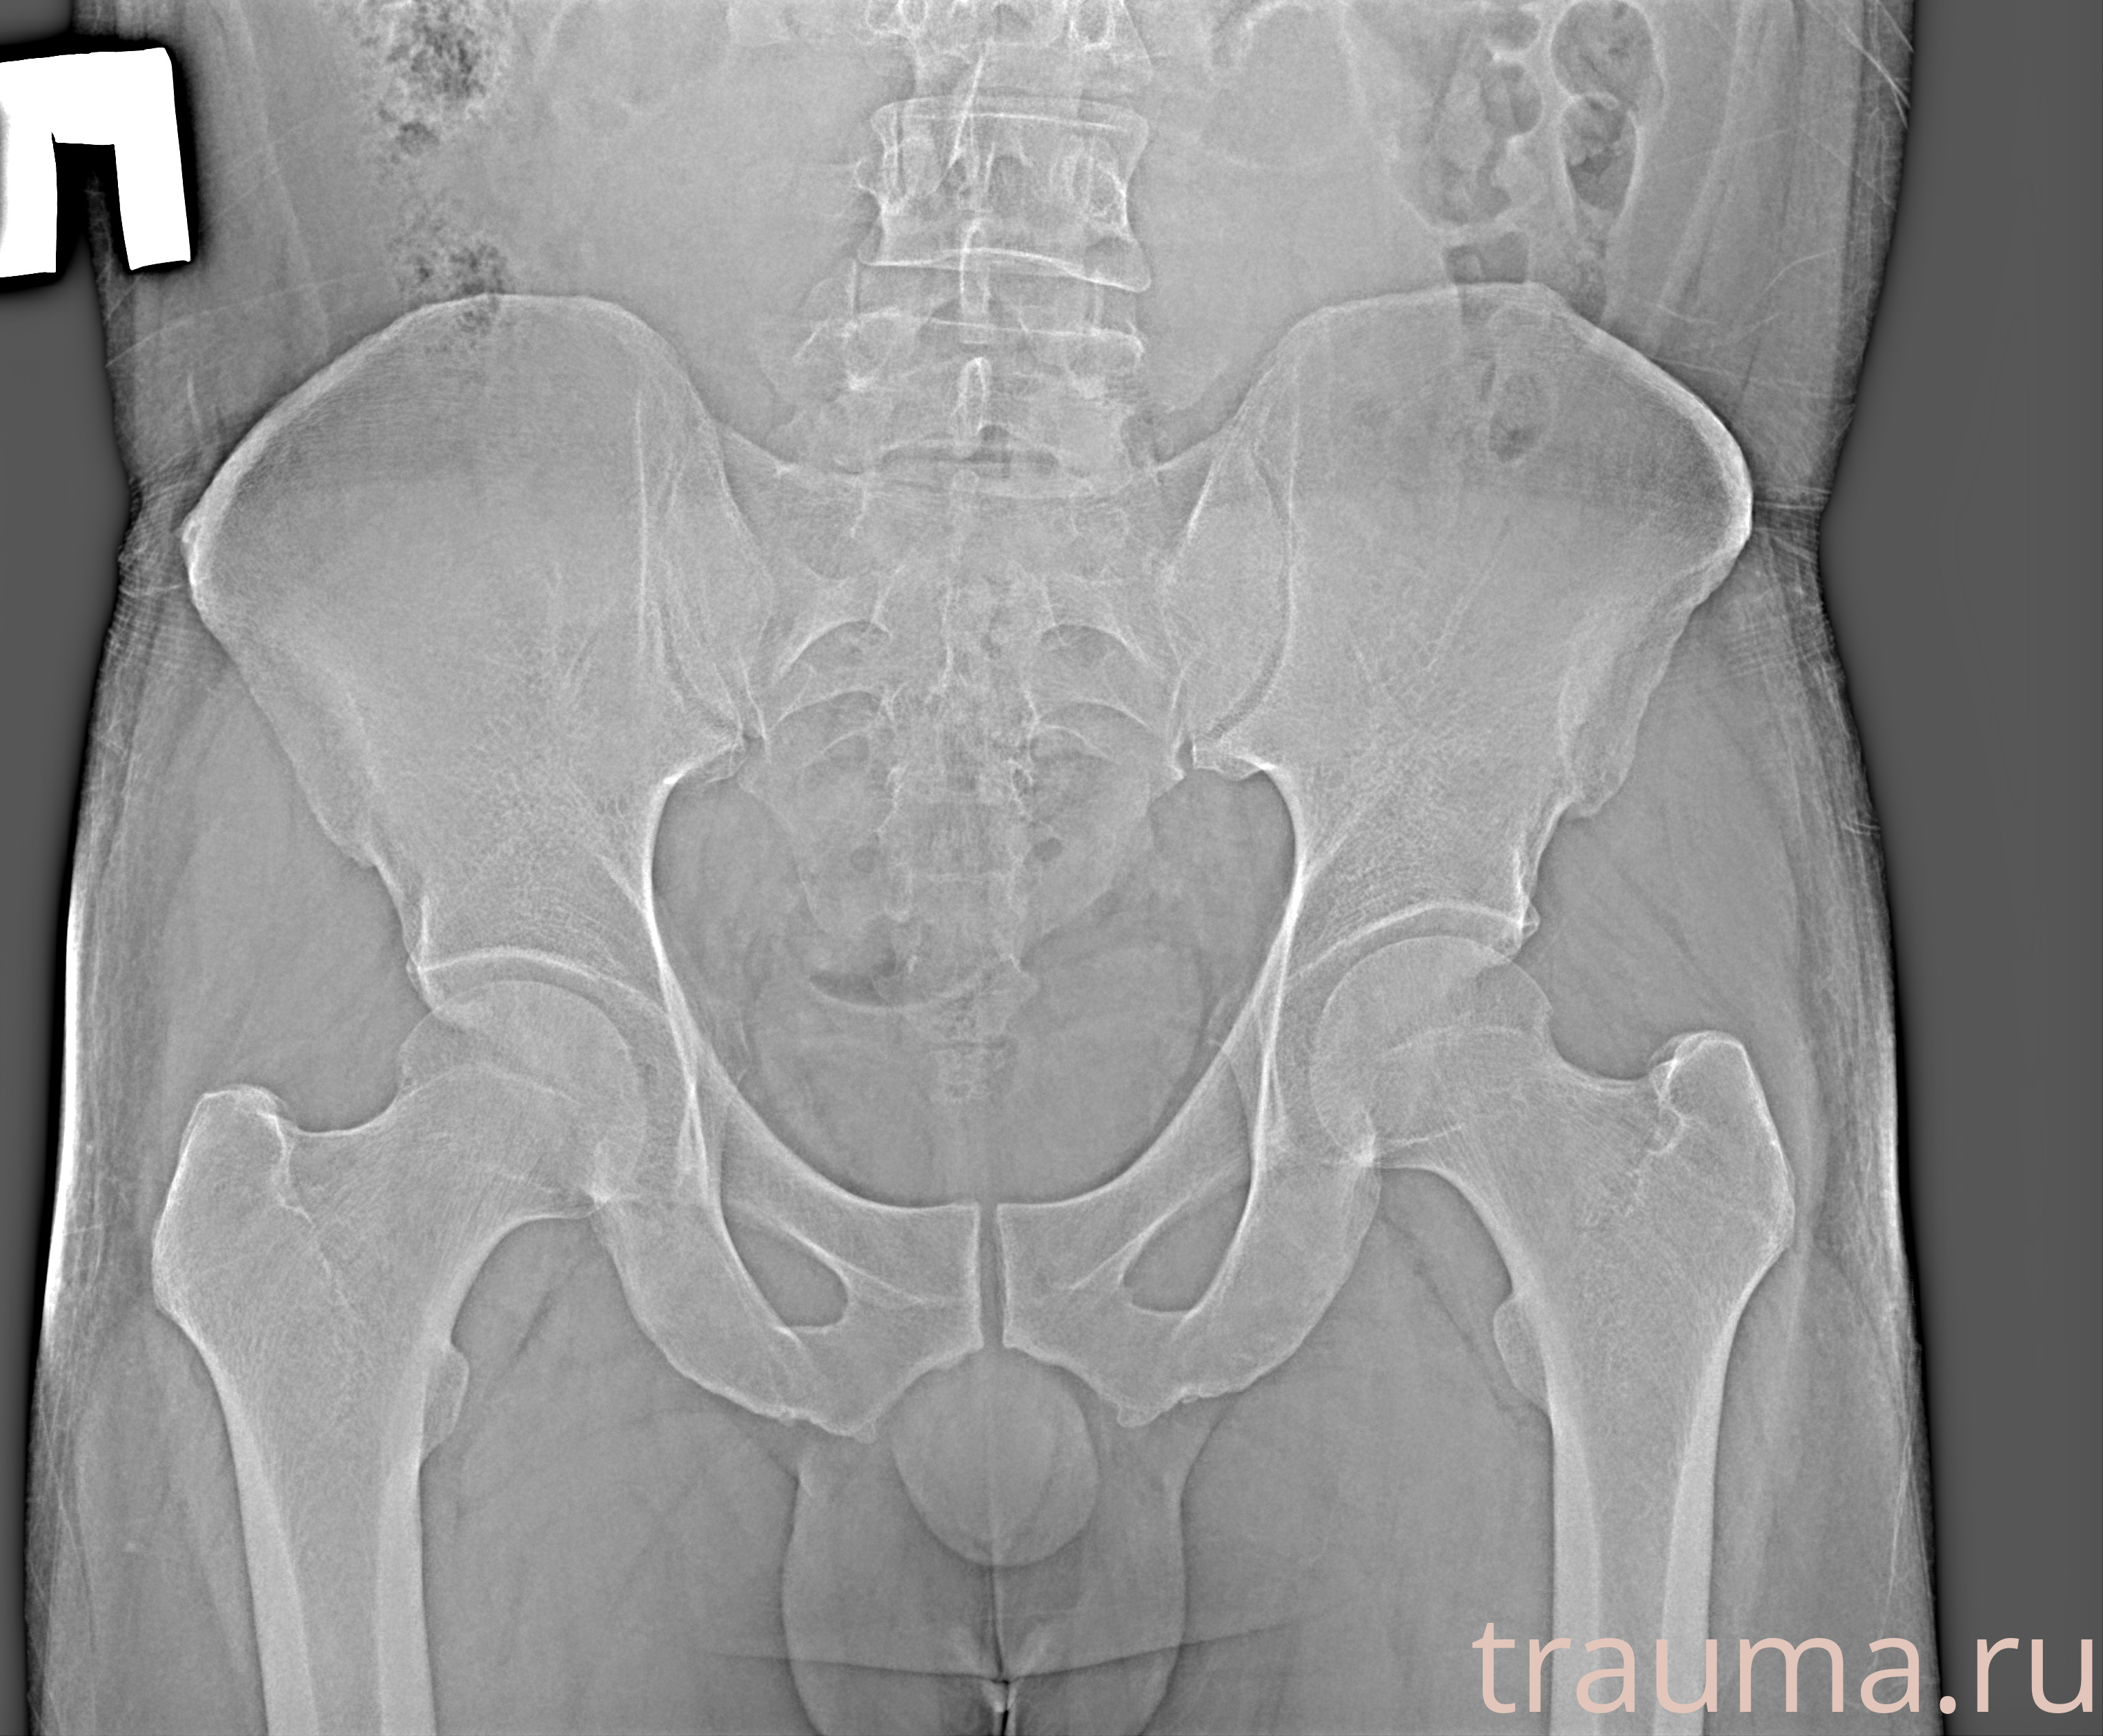

Рентгенограммы

Рентген на дому: по вашему адресу приезжает врач-рентгенолог, травматолог-ортопед с мобильным рентгеновским аппаратом, проводит диагностику травмы или заболевания, делает необходимые рентгенограммы, дает рекомендации по дальнейшему лечению. Получить качественные снимки в домашних условиях возможно благодаря уникальной методике, разработанной МосРентген Центром для института  Склифосовского